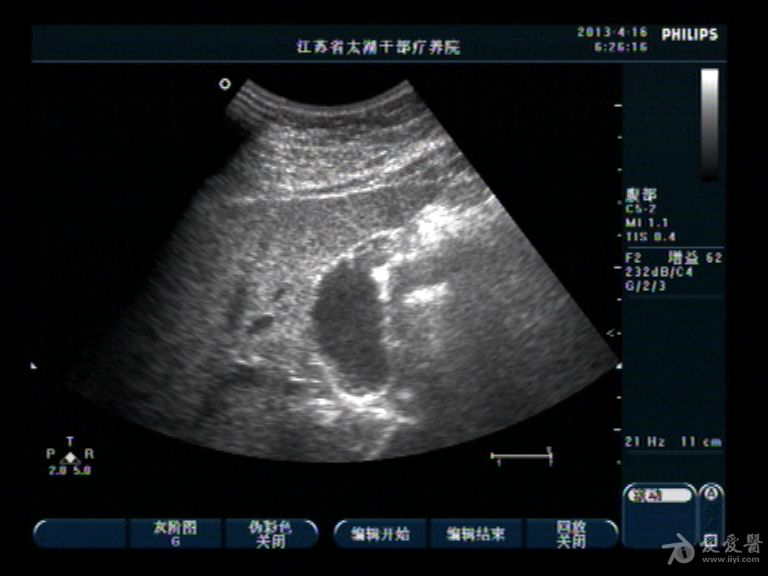

胆囊底部稍低回声区,胆泥沉积?胆囊癌不像吧?,请分析

男性,40,无右上腹痛